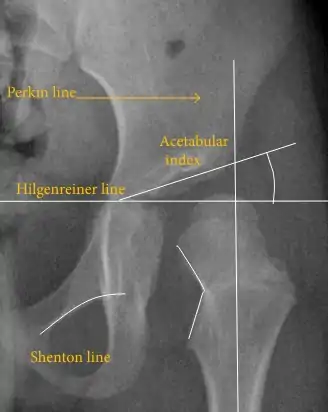

Despite the widespread of ultrasound, pelvis X-ray is still frequently used to diagnose or monitor hip dysplasia or for assessing other congenital conditions or bone tumors.[42] The most useful lines and angles that can be drawn in the pediatric pelvis assessing hip dysplasia are as follows:[42] Different measurements are used in adults.[42]